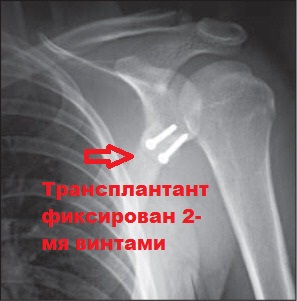

Операция включает в себя перемещение клювовидного отростка с присоединенной к нему мышцей и фиксация его к передне-нижнему краю суставной впадины.

Подобная манипуляция восполняет недостающую кость в данной зоне. Процедура имеет высокий успех, что связано с тройным эффектом операции.

В мировой медицине эта операция носит название - Операция Латарже (Latarjet - Bristow) и является наиболее часто используемой при данном виде повреждений.

Операция Латарже - 69000 рублей

- Операция Латарже

- Импланты (винты)